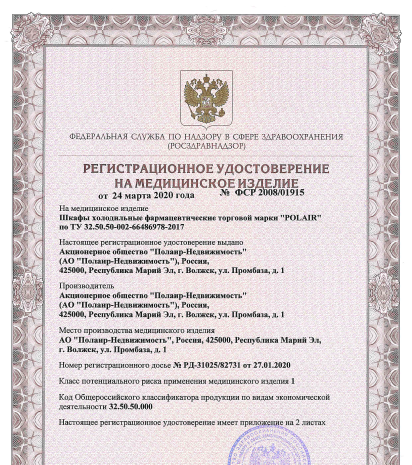

сертификаты и

разрешительная

документация

Шкафы холодильные фармацевтические торговой марки «POLAIR» имеют полный комплект разрешительной документации и изготавливаются на заказ.